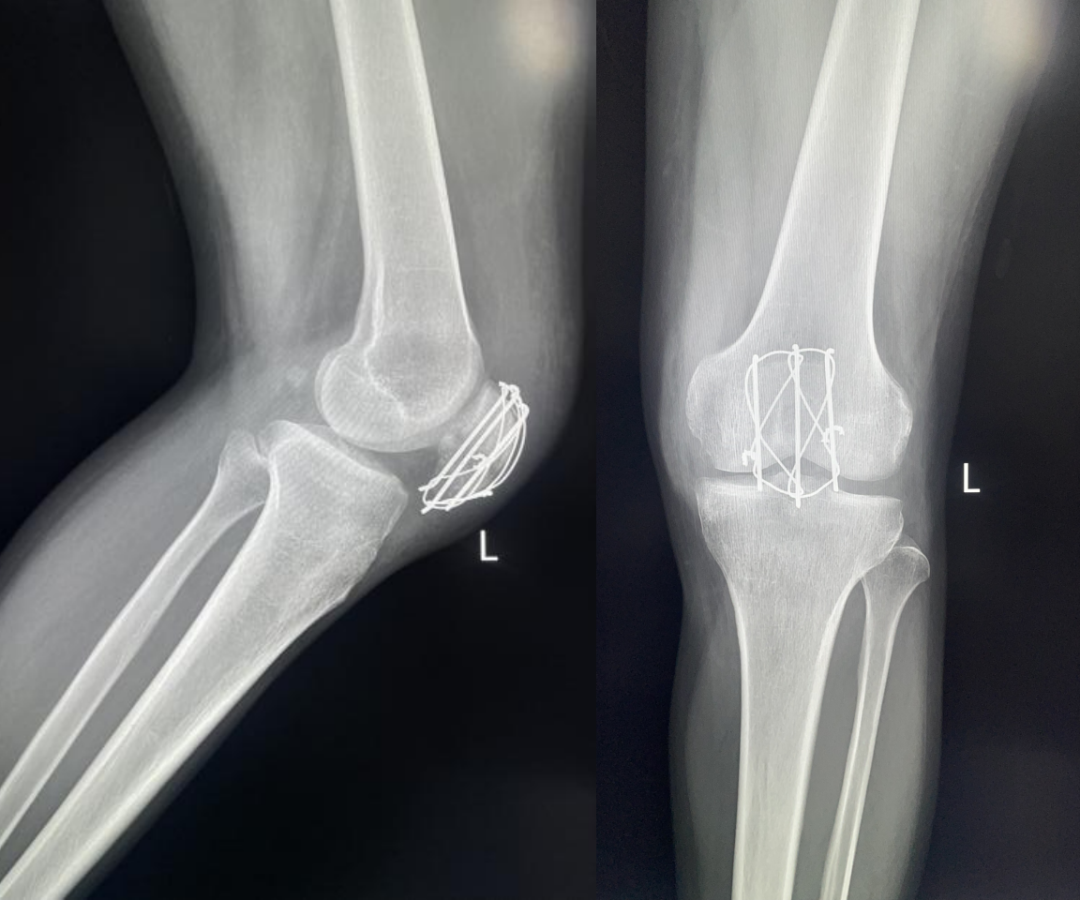

髌骨骨折只占全身骨折的 1%,治疗方式的选择和并发症的防治尤其要注意,急诊来了髌骨骨折患者,你怎么处理?髌骨是人体最大的籽骨,位于膝关节伸膝装置内。解剖特点包括近端宽大的基底和关节外的远侧尖端,前面位于关节外,后面为关节面。股直肌和股中间肌止于髌骨基底部,股内侧肌和股外侧肌止于髌骨的两侧。髌腱起于髌骨尖端,止于胫骨结节。髌骨骨折约占所有骨折的 1%,主要由直接暴力造成,如跌倒时跪地或膝关节屈曲时受到打击。典型的体征包括关节肿胀、压痛、伸膝功能部分或完全丧失。除以主诉和典型体征外,膝关节 X 线片也是必不可少的一项辅助检查,以膝关节正侧位 X 线片最常见,如果怀疑纵向骨折,膝关节屈曲 45° 时髌骨 30° 切位片可以辅助诊断。对于骨折不愈合、畸形愈合所致的关节面不平整以及髌股关节对应关系不良可采用 CT 检查。MRI 有助于诊断软骨缺损和损伤。34-B 型(部分关节内骨折,伸膝装置完整,如纵行骨折)髌骨下极骨折袢钢板结合克氏针、张力带固定 图源:作者提供

拉力螺钉加张力带钢丝固定或经胫骨结节绕髌环扎;经骨缝合撕裂的肌腱加髌骨和胫骨结节间钢丝环绕以加固缝合;袢钢板固定。无移位采用非手术治疗;移位并且单纯骨折采用横向拉力螺钉固定,骨质疏松患者需加环扎固定;对于多骨折块(星状)则采用髌骨环扎加张力带进行固定。克氏针加张力带钢丝;有第三个骨折块则采用拉力螺钉或克氏针加张力带钢丝固定;对于 4 个或 4 个以上的骨折块采用克氏针加螺钉加张力带钢丝进行固定;对于严重粉碎和软骨面广泛破坏的髌骨骨折,髌骨部分或完全切除也是一种可行的办法。

术中切开显露髌骨时,最理想的的分离层面为皮下筋膜和伸膝装置之间,如若在皮肤和皮下筋膜之间进行分离,可能会造成伤口边缘坏死。对于开放性髌骨骨折应及时给予清创处理,对于闭合性髌骨术后感染患者应及时进行清创灌洗直至伤口愈合。如有深部感染则推荐长期使用抗生素。透明降解物会产生轻重不等的无菌性滑膜炎,这很难和感染相区分。需行关节镜检查来确定。在进行克氏针固定髌骨时,克氏针的末端应剪短,否则有穿破皮肤以及术后活动时疼痛的风险。髌骨骨折术后内植物至少在损伤后 9 ~ 12 个月才能取出。高密度的骨皮质需要这么长时间才能愈合,从而能在无保护情况下承受高张力。必须防止这一并发症的发生,因为会导致膝关节屈曲严重受限。用环扎钢丝来保护髌腱时,有可能因为错误估计髌腱长度而造成髌骨低位。髌骨的正常位置可以参照健侧膝关节的 X 线片。屈曲受限的患者需要进行强化理疗。如果在数月内运动的范围没有增加,下一步可行关节镜下松解,去除髌上囊的挛缩瘢痕。如果髌骨已切除,则可能出现肌腱断裂的晚期并发症。髌骨软骨面的严重损伤、关节面不平整的继发性损伤以及髌股关节受力的改变,都将导致创伤性关节炎的发生。如果髌骨韧带附着位置太靠前方,会使髌骨下极位置靠后,也将导致创伤性关节炎。在前一种情况下,可以行关节镜下清理;后一种情况下需改变韧带附着点位置。髌骨术后应及时有效地进行膝关节活动锻炼,一般在术后 3 月时膝关节可屈曲 120° 以上,若术后 3 月时膝关节弯曲角度仍然小于 90°,建议进行辅助康复训练,必要时以手术松解。